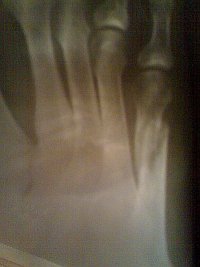

Конкретно ответить не могу, не видя ребенка, но так быывает. Возможно само пройдет. К врачу.У сына (13 лет) был перелом 3 и 4 плюсневых костей без смещения. На 24 дня наложили лангету, которую сняли 2 дня назад. Сейчас не наступает на пятку, говорит, что очень больно, и костыль не бросает. А сегодня поскользнулся и сильно наступил на всю стопу, после этого нога болит и в состоянии покоя. В области перелома боли нет. Врач из процедур рекомендовал только ванночки с морской солью. Подскажите является ли это обычной реакцией после снятия гипса и что можно порекомендовать в данном конкретном случае.